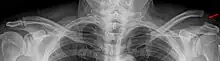

Ostéologie

A : ligament acromio-claviculaire. B : acromion. C : ligament coraco-acromial. D : ligament coraco-huméral. E : tendon du long chef du biceps. F : tubercule mineur de l'humérus, ou trochin. G : capsule ligamentaire. H : processus coracoïde. I : ligament coraco-claviculaire (comportant le trapézoïde et conoïde). J : clavicule. K : tubercule majeur, ou trochiter

Le complexe articulaire de l'épaule met en relation quatre os :

- le manubrium sternal (ainsi que le premier cartilage costal) ;

- la clavicule ;

- l'omoplate (scapula) ;

- la tête humérale.